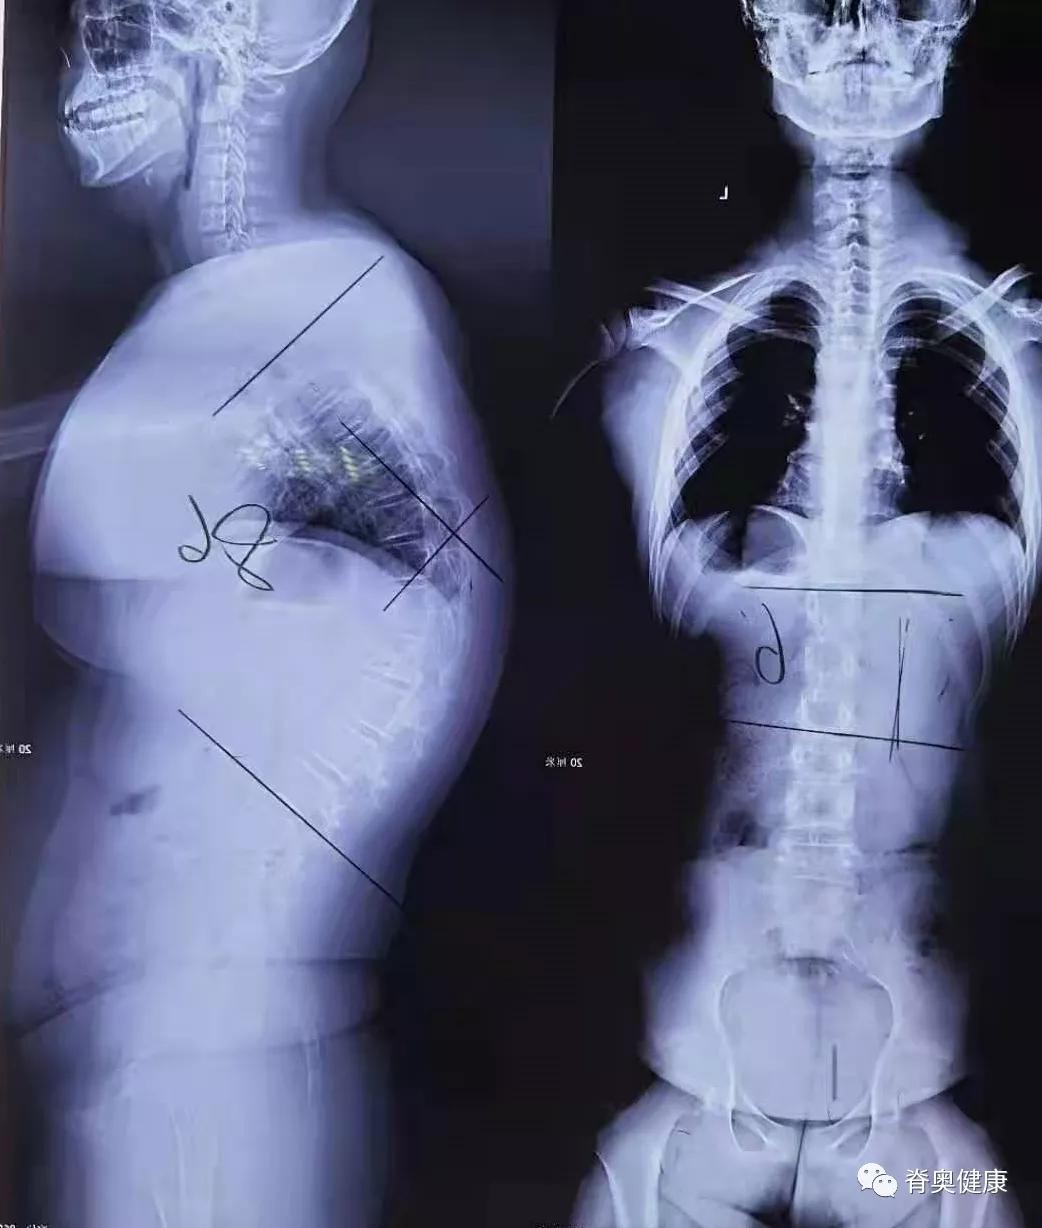

对脊柱后凸的青少年需定期复查,包括X光片,直到骨骼发育成熟。注意预防后凸进展和畸形加重,后凸有好转需热塑调整胸椎后凸矫形器,积极配合治疗,胸椎后凸将得到非常大的矫正。